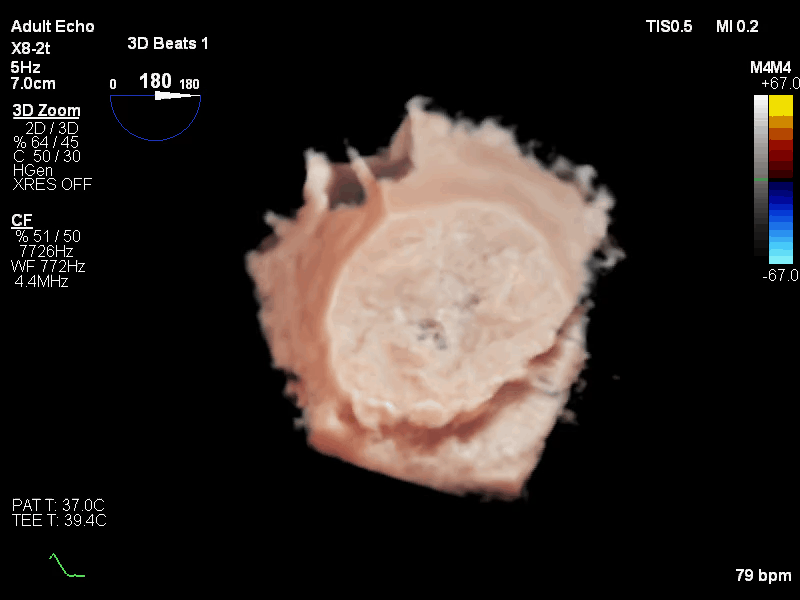

手术采用心尖入路,术中利用TEE引导确定心肌穿刺点,穿刺后导丝顺利跨二尖瓣进入左心房;TEE引导反复确认导丝未从腱索中穿过后,沿导丝推进输送系统,开始释放瓣膜;在二维和三维超声引导下完成同轴定位、D型定位后,完全释放瓣膜,撤出输送系统;最后根据血压调整瓣膜张力,进行心尖固定。

术后即刻超声心动图评估显示二尖瓣瓣膜释放位置精准,锚定稳固,无瓣周漏和中心反流,瓣膜工作形态良好,手术取得圆满成功。